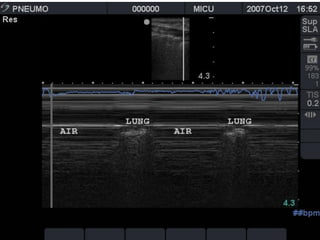

the "seashore sign" (Fig.3).

Absent lung sliding

Exaggerated horizontal artifacts

Loss of comet-tail artifacts

Broadening of the pleural line to a band

The key sonographic signs of

Pneumothorax

 Multiple studies have shown ultrasound to be more

sensitive than supine CXR for the detection of

pneumothorax.

 Sensitivities ranged from 86-100% with specificities from

92-100%.

 Furthermore USS can be performed more rapidly at the

bedside.

 Detection with ultrasound relies on the fact that free air is

lighter than normal aerated lung tissue, and thus will

accumulate in the nondependent areas of the thoracic

cavity. (ie anteriorly when patient is supine).

To get the lung window

 Patient should be supine.

 Use high frequency linear

array or a phased array

transducer.

 Position in the

midclavicular line, 3rd to 4th

intercostal space with

probe oriented

longitudinally.

 Position between ribs.

himaP  Multiple studieshave shown ultrasound to be more sensitive than supine CXR for the detection of pneumothorax.  Sensitivities ranged from 86-100% with specificities from 92-100%.  Furthermore USS can be performed more rapidly at the bedside.  Detection with ultrasound relies on the fact that free air is lighter than normal aerated lung tissue, and thus will accumulate in the nondependent areas of the thoracic cavity. (ie anteriorly when patient is supine).

To get thelung window  Patient should be supine.  Use high frequency linear array or a phased array transducer.  Position in the midclavicular line, 3rd to 4th intercostal space with probe oriented longitudinally.  Position between ribs.